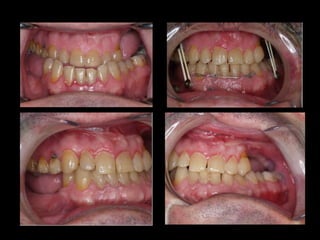

Mejor planificación estética Y funcional mandibular en el auto trasplante de tejidos. Disminución del tiempo quirúrgico en el modelado de la placa mandibular 60´. Mantenimiento de la relación céntrica. Mayor exactitud con la “técnica en espejo”.

Mejor planificación estéticaY funcional mandibular en el auto trasplante de tejidos. Disminución del tiempo quirúrgico en el modelado de la placa mandibular 60´. Mantenimiento de la relación céntrica. Mayor exactitud con la “técnica en espejo”.